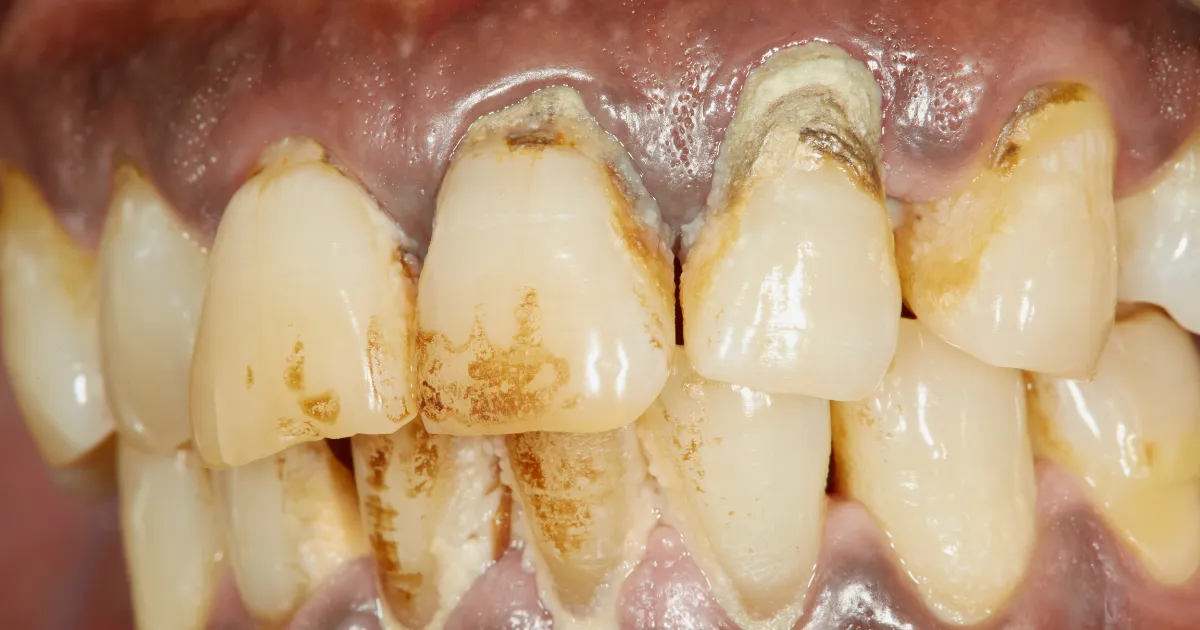

歯周病は、歯と歯茎の間に細菌が入り込むことで炎症が起き、歯茎が腫れたり、出血が見られる病気です。

進行すると歯を支える骨が溶けていき、極端な話歯が抜け落ちるリスクが高まります。

親知らずは、前から数えると8番目で位置的に歯磨きが届きにくく、磨き残しが発生しやすいため、歯周病リスクが高くなります。

また、親知らずが歯茎に部分的に埋まっている場合や、横向きに生えている場合、食べかすや歯垢がたまりやすく、細菌の温床となります。